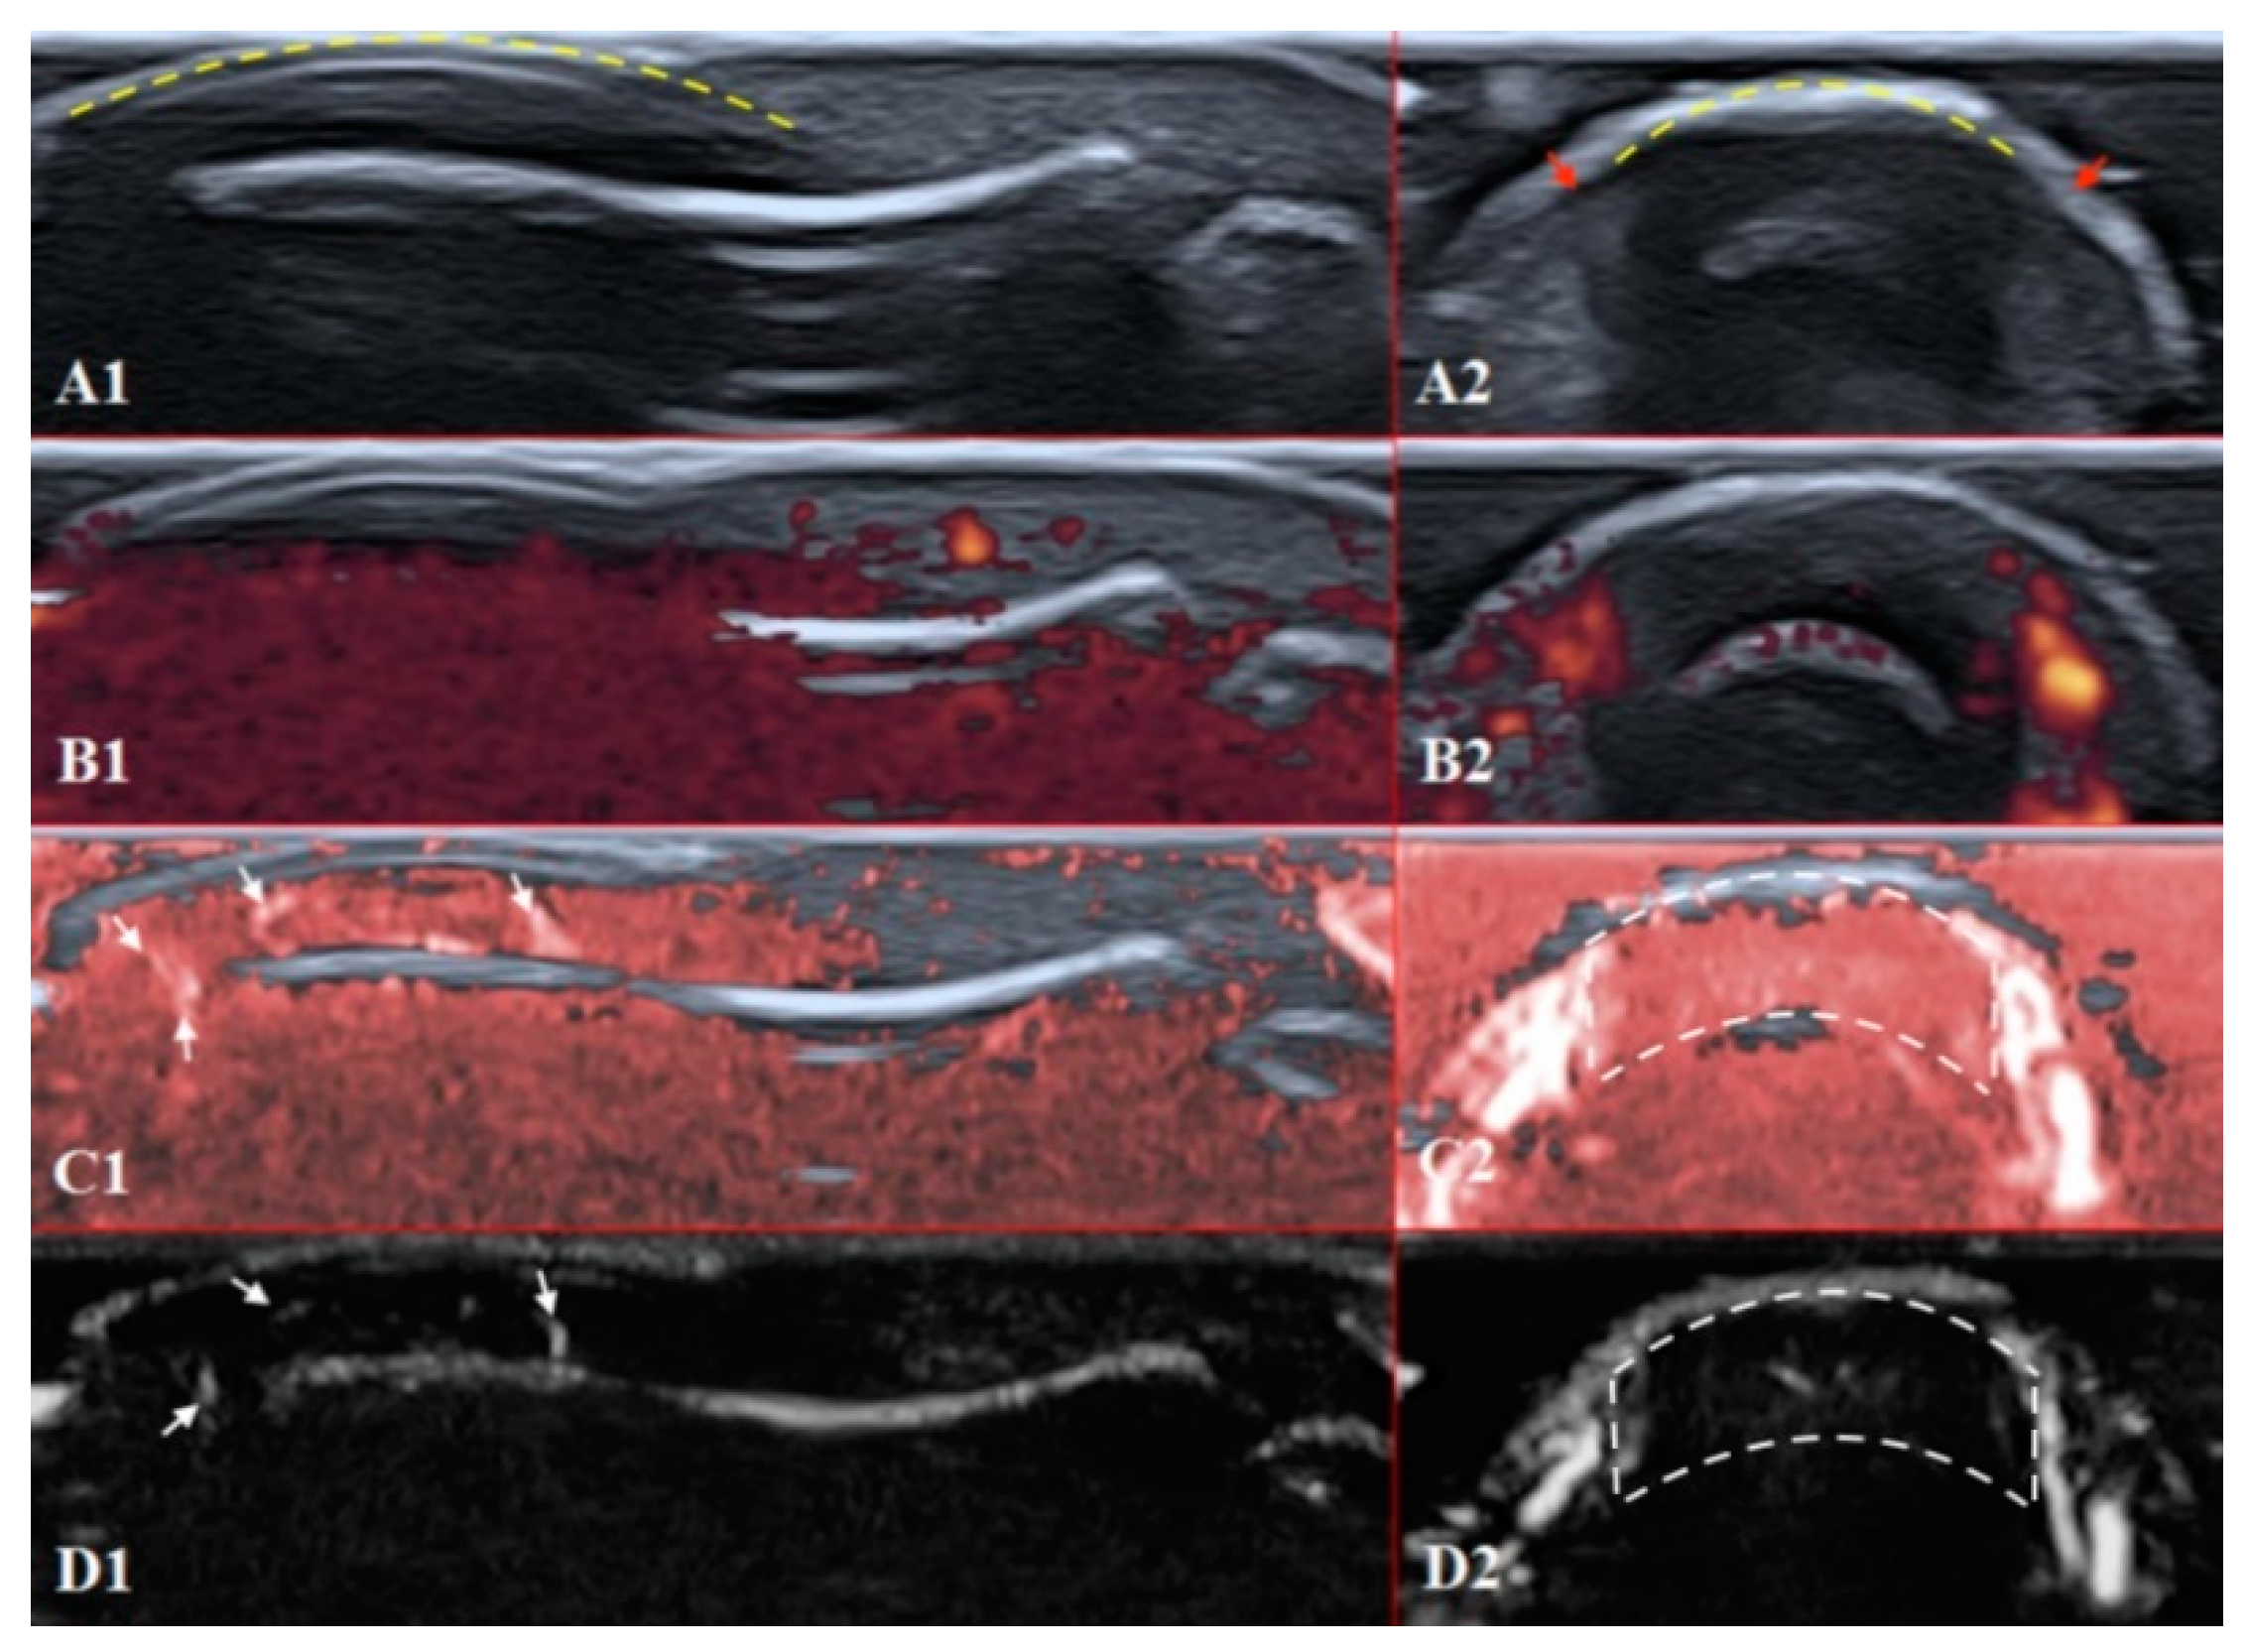

Figure 4. Ultrasound images of the healthy fingertip of the second finger of a hand: (A1,A2) B mode/grayscale; (B1,B2) PD; (C1,C2) cSMI; (D1,D2) mSMI. The yellow dotted lines mark the nail. Sagittal scans (B1D1) in the midline of the fingertip show vascularity from the deep layers of the nailbed to the end of fingertip pulp. The main landmarks for all transverse scans (B2D2) are lateral nailfolds (A2 red arrows), which unite in the middle of the proximal nailfold and become a convex line.

The structures of the nailfold are too small to assess by a conventional US. Thus, adequate sonographic evaluation is dependent on high-resolution techniques and high-frequency linear array probes. We used a diagnostic ultrasound system (CANON TUS-AI800, Canon medical systems Corp., Shimoishigami, Otawara-shi, JAPAN) equipped with a linear transducer with the following settings: 24 MHz ultrahigh-frequency (Canon medical systems Corp., Shimoishigami, Otawara-shi, JAPAN). Sagittal (dorsal volar) and transverse scans of fingertips were performed on a healthy volunteer (Figure 4) and a patient with late-course SSc (Figure 5). ROI was located between the fingernail and the bony surface of the distal phalanx. Up-to-date versions of SMI equipment provide a direct-control scale function. Therefore, the investigators do not need to worry about ROI.

PD and SMI settings have to be standardised for all evaluations. There is an appropriate option to differentiate primary Raynaud’s syndrome from its secondary development by setting the gain. Martinoli et al. suggested increasing the gain maximally and then slowly lowering it until the noise disappears and true signals remain [20]. Rubin offered a converse way to raise the gain manually until the colour box becomes filled with signals and a true flow is distinguished from the background as the next highest signal [21]. The method by Rubin seems to be a quick and comfortable technique to check vascularity in fingertip pulp and nailfold zones (Figure 6 and Figure 7). It takes less time to evaluate vascularity by SMI modes rather than the conventional PD technique due to its higher sensitivity for low flow. Monochrome SMI is a comfortable mode for the evaluation of vasculature and even vascular torsions, as the true flow has more power, and it is easier to separate these dots from the background of random noise artefacts (Figure 4D2).